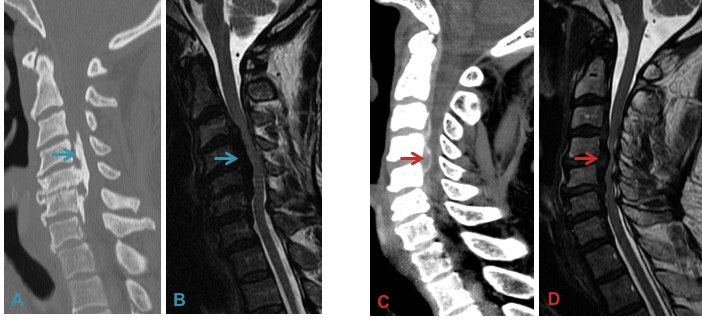

h) Ossification of posterior longitudinal ligament – causes spinal canal stenosis. CT helps in confirmation as MRI may not demonstrate it accurately all the time. T2 hypointensity on MRI along the PLL may or may not represent calcification; hence perform a confirmatory CT in any MRI where you suspect OPLL.

Ossification of the Posterior Longitudinal Ligament (OPLL: A & B) usually results in spinal stenosis over multiple contiguous levels. Multilevel disk degeneration (C & D) can resemble OPLL on MRI (B vs D) and the diagnosis is thus best made on CT (A vs C).